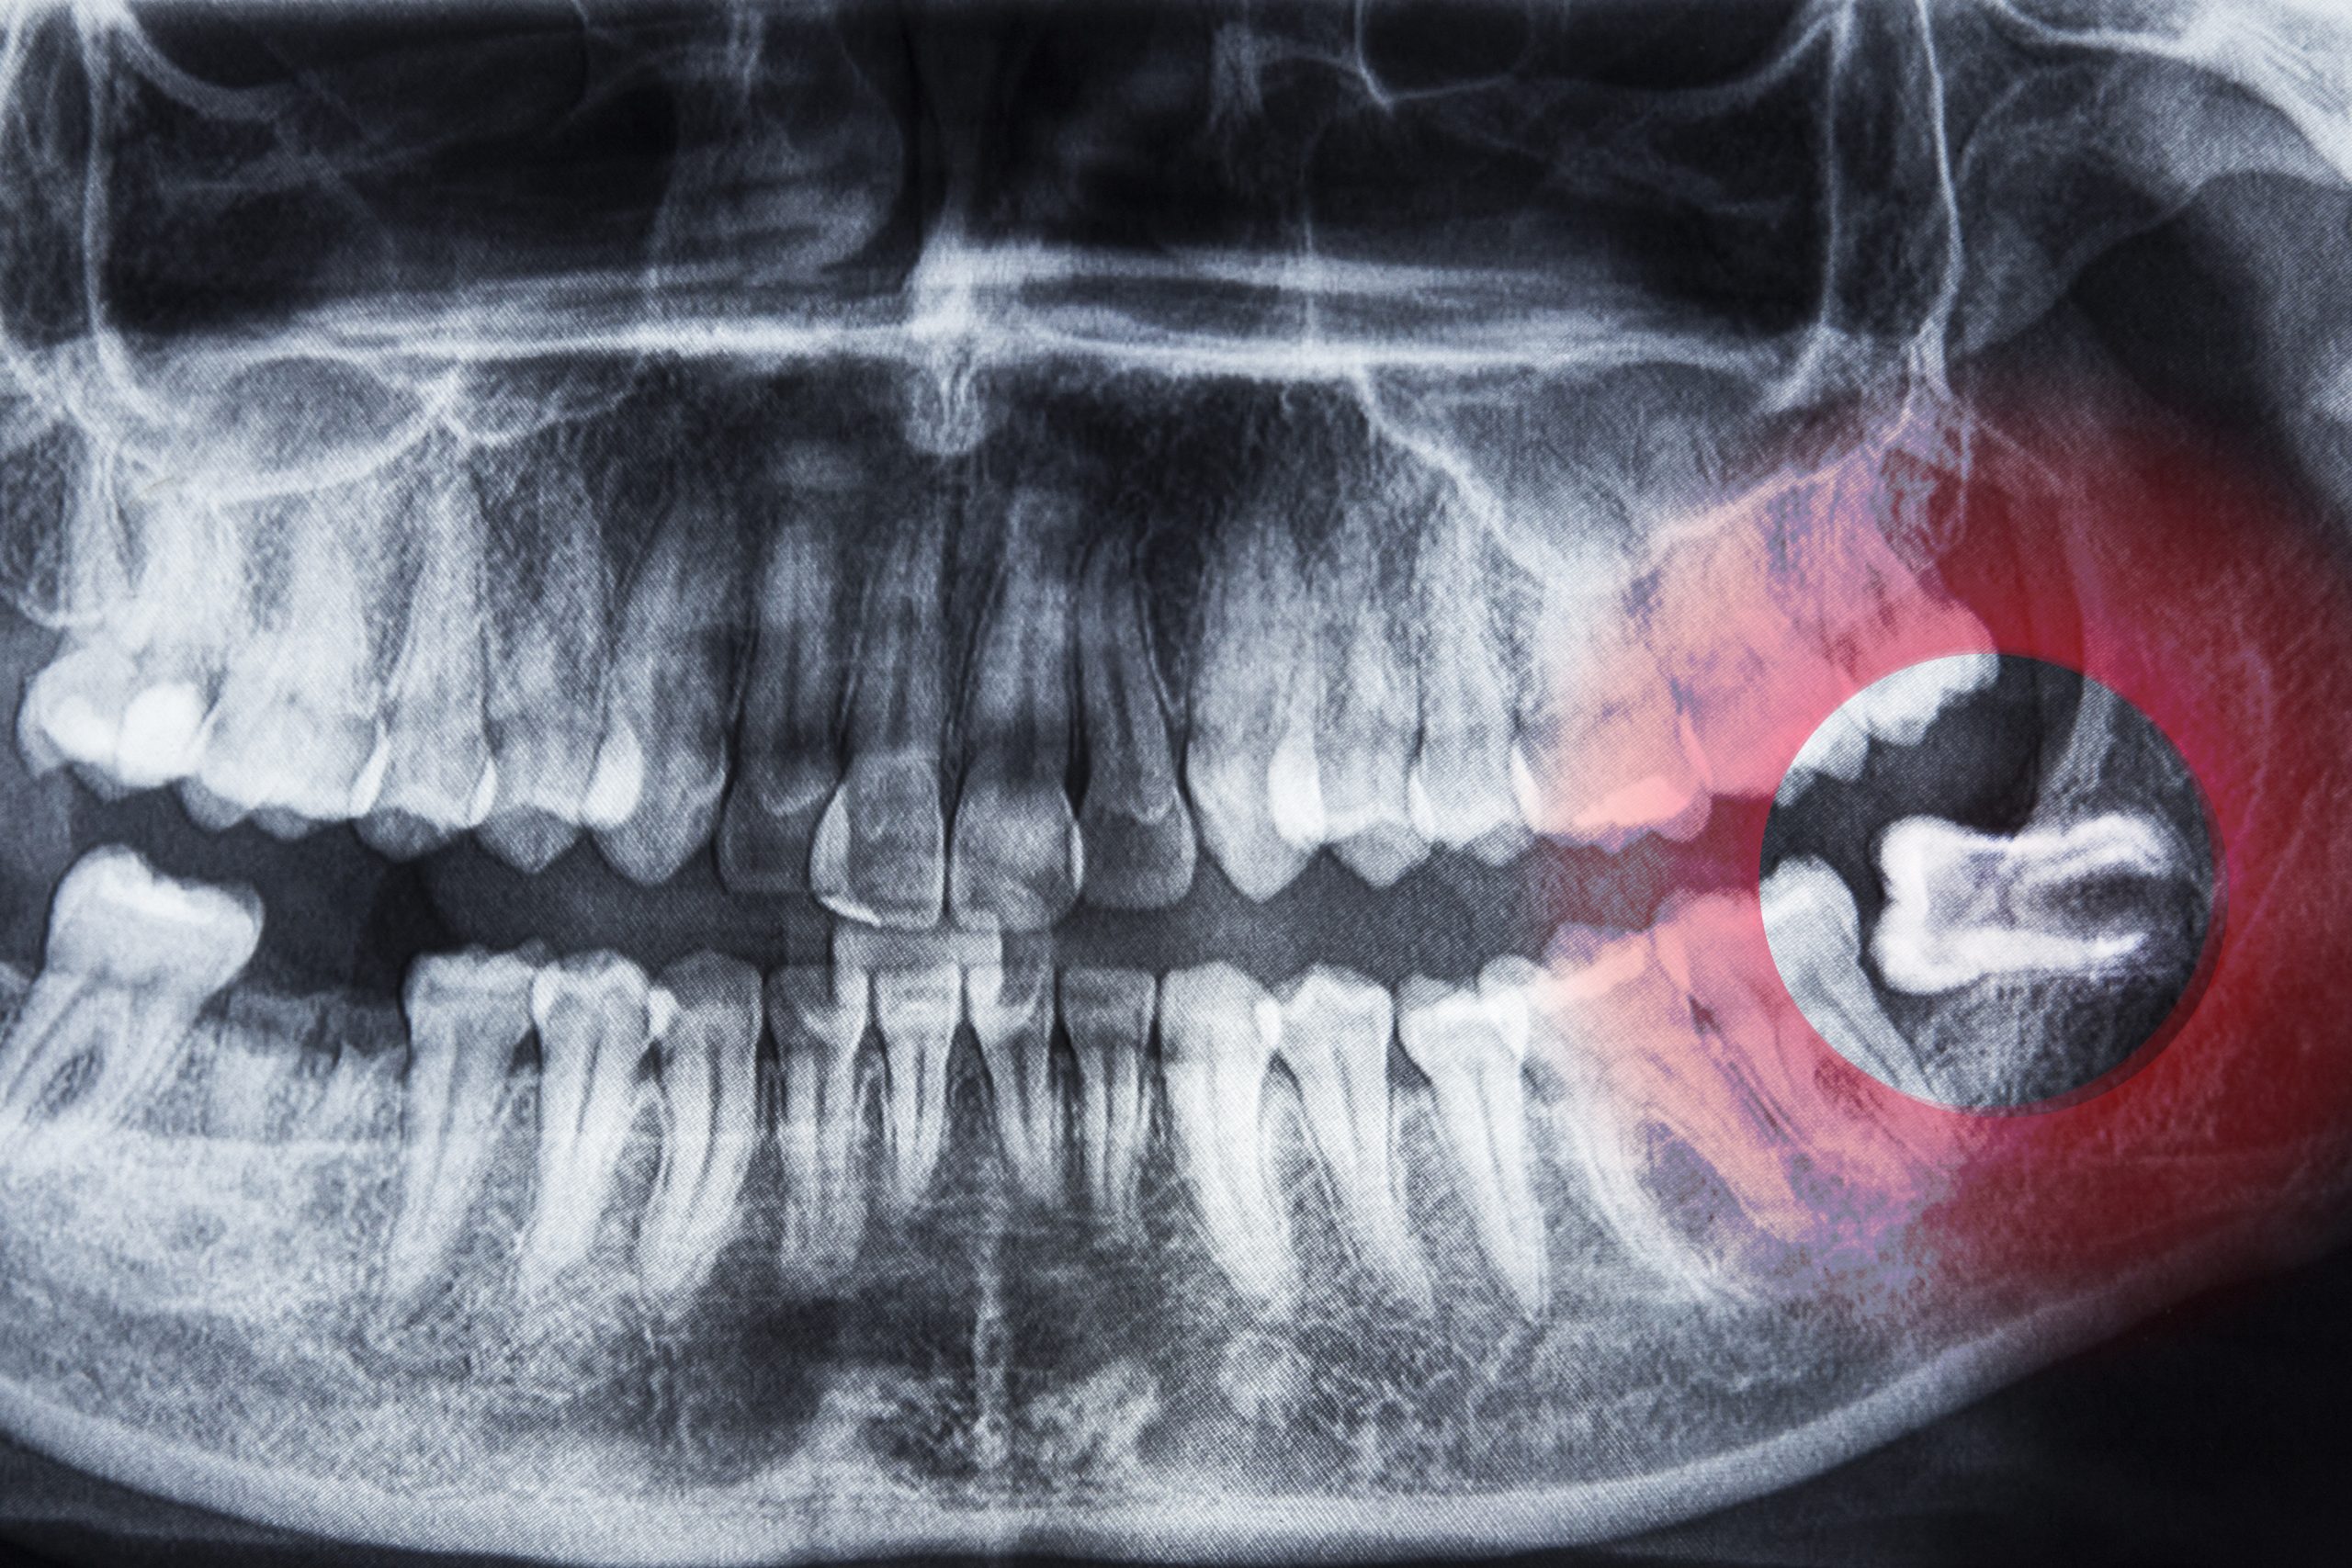

¿Cuándo hay que extraer las muelas del juicio?

La erupción de las muelas del juicio es un temor muy común entre las personas, pues muchas creen que va directamente relacionado con una extracción, pero lo cierto es que,